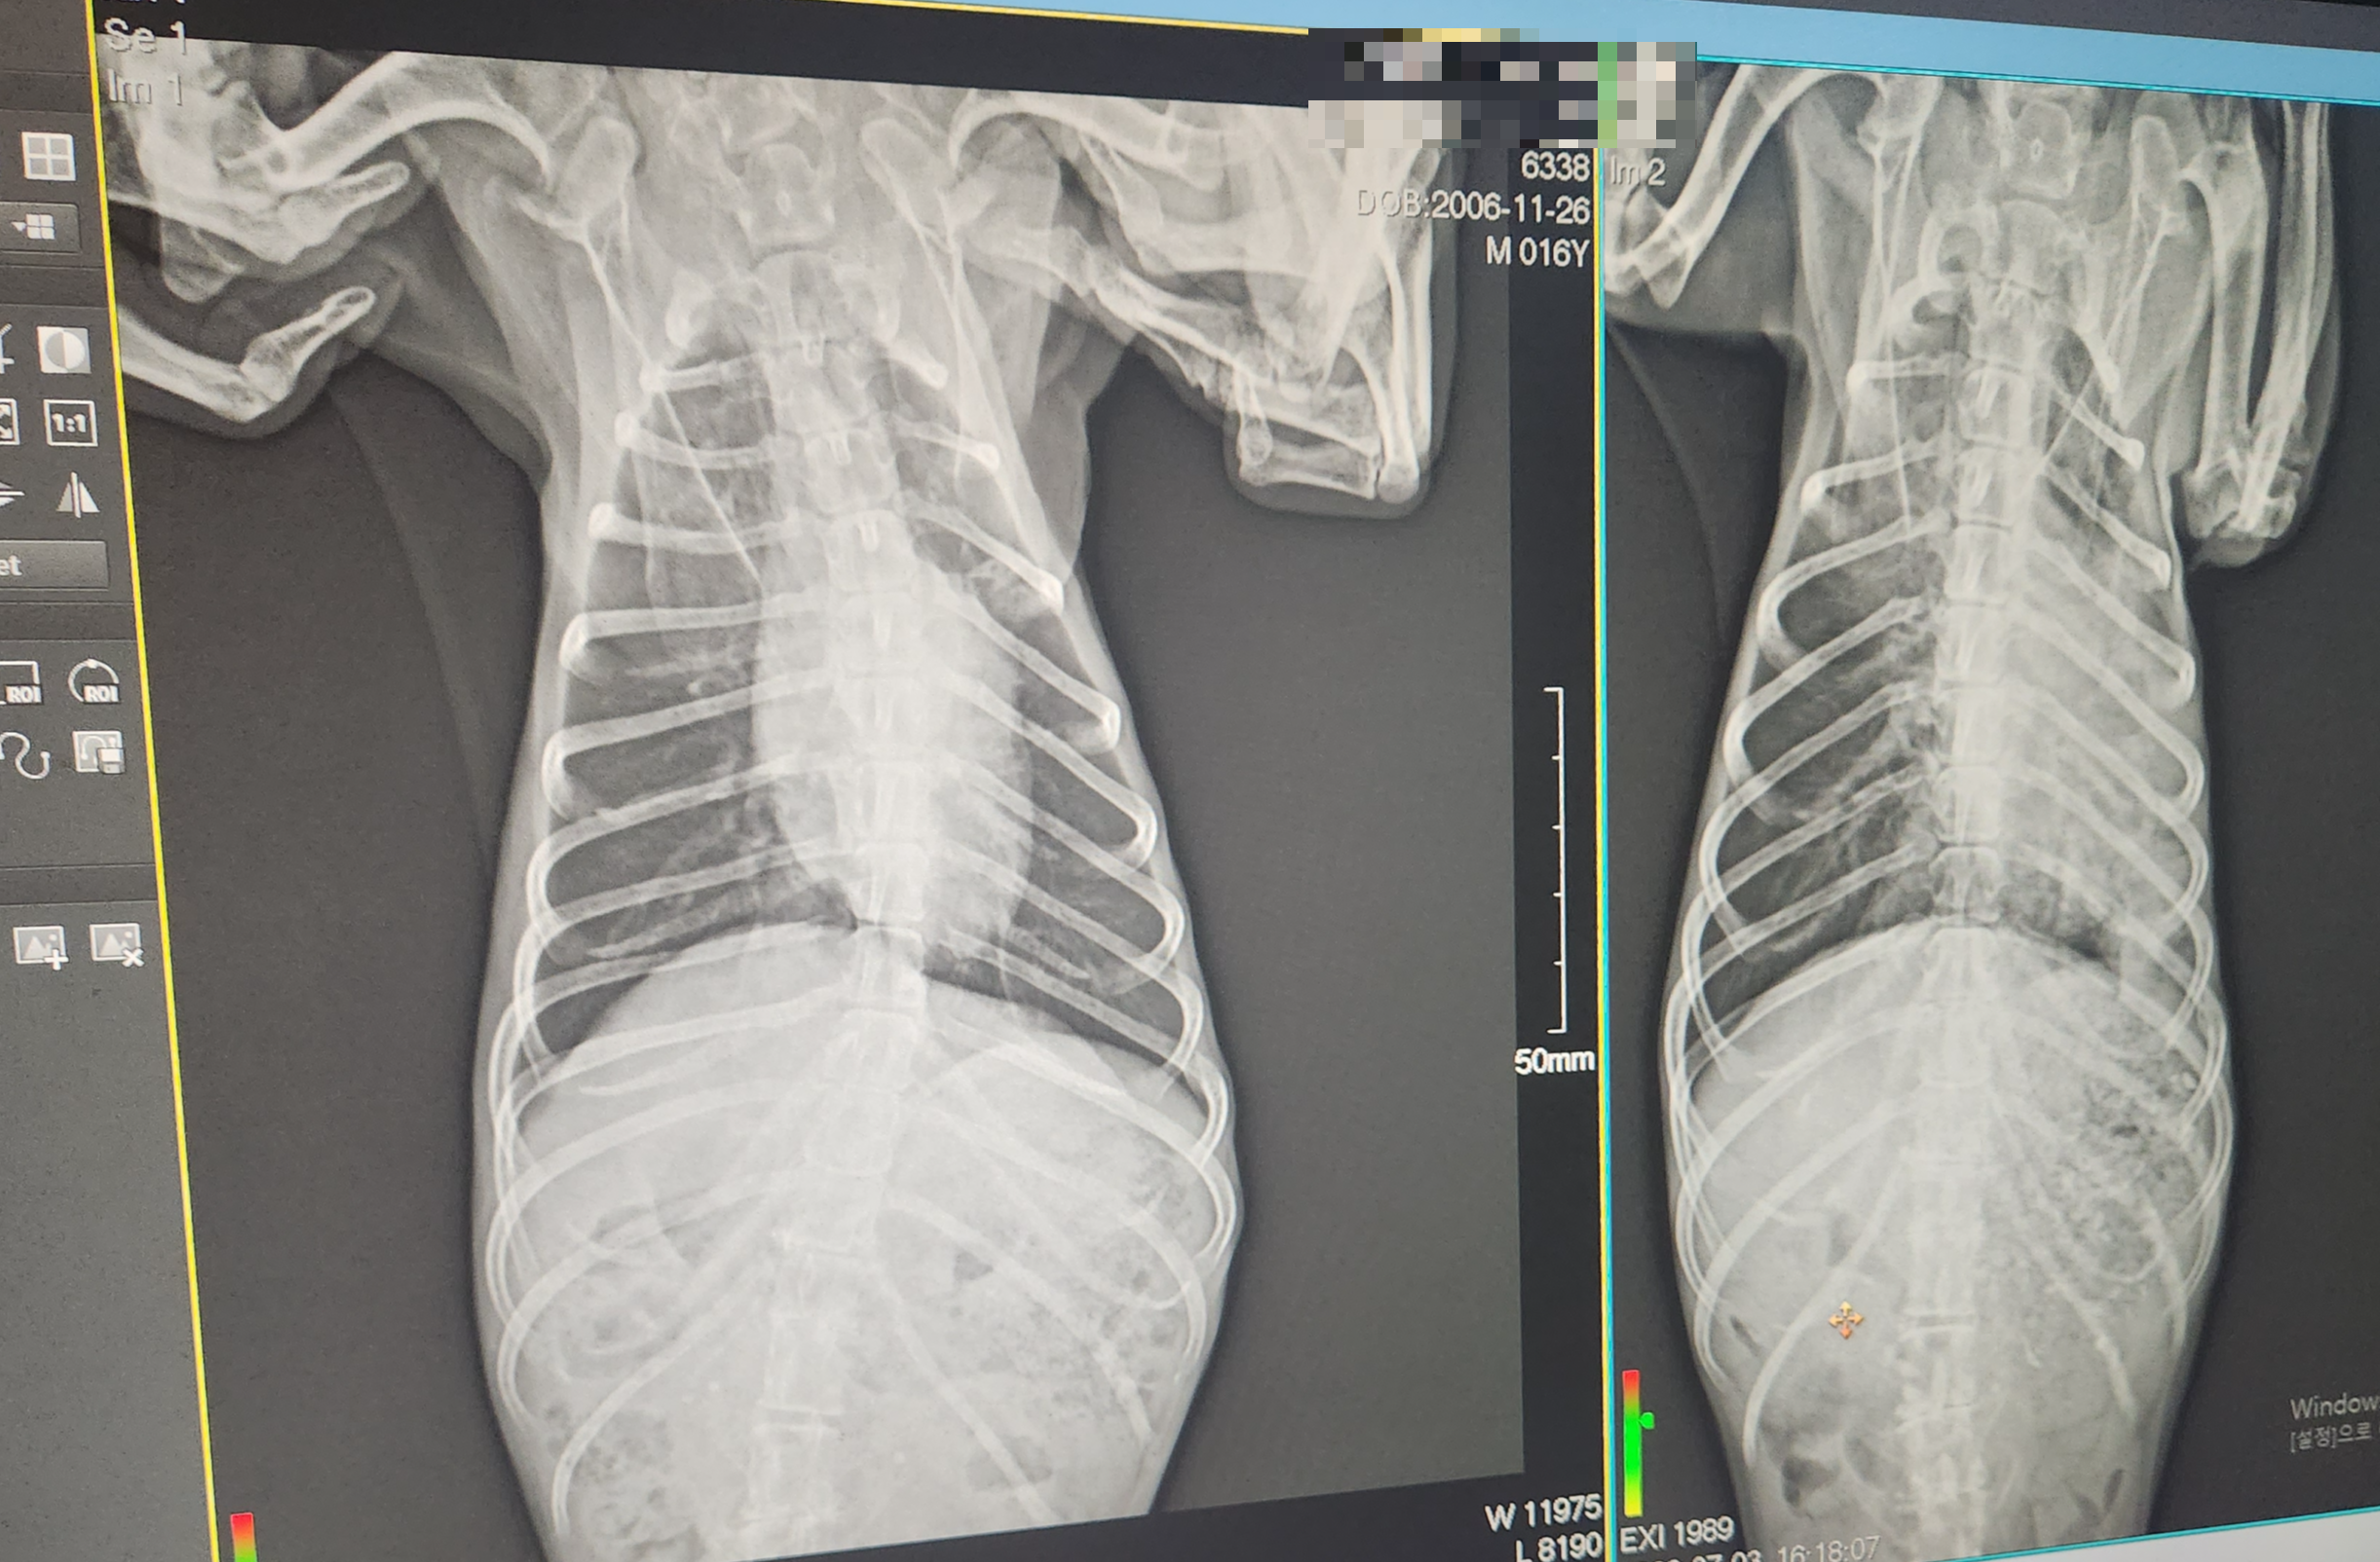

수의사님이 우리 아이 청진 결과 엑스레이와 피검사가 필요하다고 하셔서 엑스레이와 피검사를 했습니다. 엑스레이 검사 결과 폐렴, 피검사 결과는 염증수치 200으로 나왔습니다. 우리 아이가 위험한 상황이라서 바로 산소 방에 넣고 호흡기 주사 및 수액 치료에 들어갔습니다. 아주 위험한 상황이라서 조금만 늦어도 큰일 날뻔했습니다. 문제는 집 근처 동물병원이 24시간 운영하지 않아서 24시간 운영하는 2차 동물병원으로 전원을 가게 되었습니다.

저희 아이 같은 경우 폐렴치료를 하기 위해서 3일 정도 입원 치료를 했습니다. 입원을 3일 정도 했어요. 24시간 산소방에서 수액과 주사 그리고 네뷸라이저 호흡기 치료를 했습니다. 아이의 상태를 확인을 하기 위해서 엑스레이 촬영도 같이 했습니다. 병원에 아이를 두고 집으로 왔는데 집에 아이가 없으니 너무 허전했어. 이틀 정도 입원했을 때 수의사 원장선생님이 많이 괜찮아졌다고 하시더라고요 그리고 하루뒤에는 이제 퇴원해도 되겠다고 말씀하셔서 퇴원을 했습니다. 퇴원을 하고 집에서 아침저녁으로 약물 치료를 했어요

퇴원 후 입원한 병원에서 처방받은 약을 1주일 정도 먹였습니다. 아침저녁으로 12시간 간격으로 먹였는데요. 일주일 정도 먹으니 기력이 조금씩 회복을 하더니 활동량이 늘었어요 밥이나 간식도 잘 먹고 물도 잘 먹고 변도 괜찮고 약을 더 처방을 받기 위해서 처음에 내원했던 집 근처 동물병원에 가서 검사를 받고 똑같은 약을 1주일치 더 차방 받아 왔습니다. 총 2주간 약을 먹었습니다. 약의 성분은 소염제인 것 같은데 자세히는 모르겠습니다. 2주간 약을 먹고 어제 병원에 가서 엑스레이와 피검사 결과 완치 되었고 더 이상은 약을 먹지 않아도 된다는 소견을 받았습니다. 엑스레이 결과 말끔하게 다 나았습니다.^^